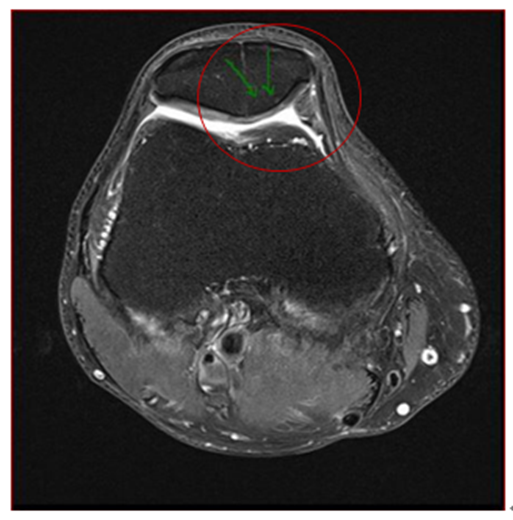

2018年10月的复查MRI显示半月板撕裂、进行中的髌骨骨髓水肿(BME)和软骨下囊肿(SBCs)以及进一步扩大腘窝囊肿的进展(如图1a和1b)。骨科医生建议采用关节镜下半月板切除术、清创术和未来的膝关节置换术进行手术干预。

图1a:间充质干细胞治疗前T2 MRI显示髌骨骨髓水肿和囊肿;1b:腘窝囊肿

图片来源:【1】